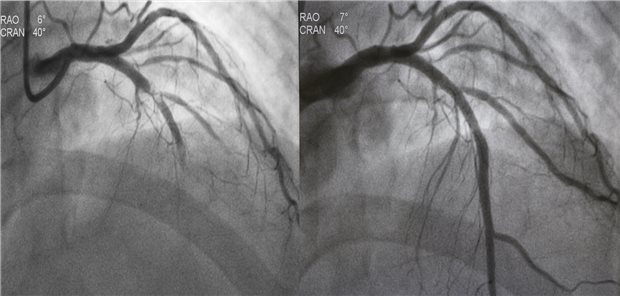

Objektives Messen statt subjektiven Schätzens kann die Resultate perkutaner Koronarinterventionen verbessern. Ein Instrument dafür ist die intravaskuläre Ultraschallsonografie. Es scheint aber auch eine Alternative zu geben.